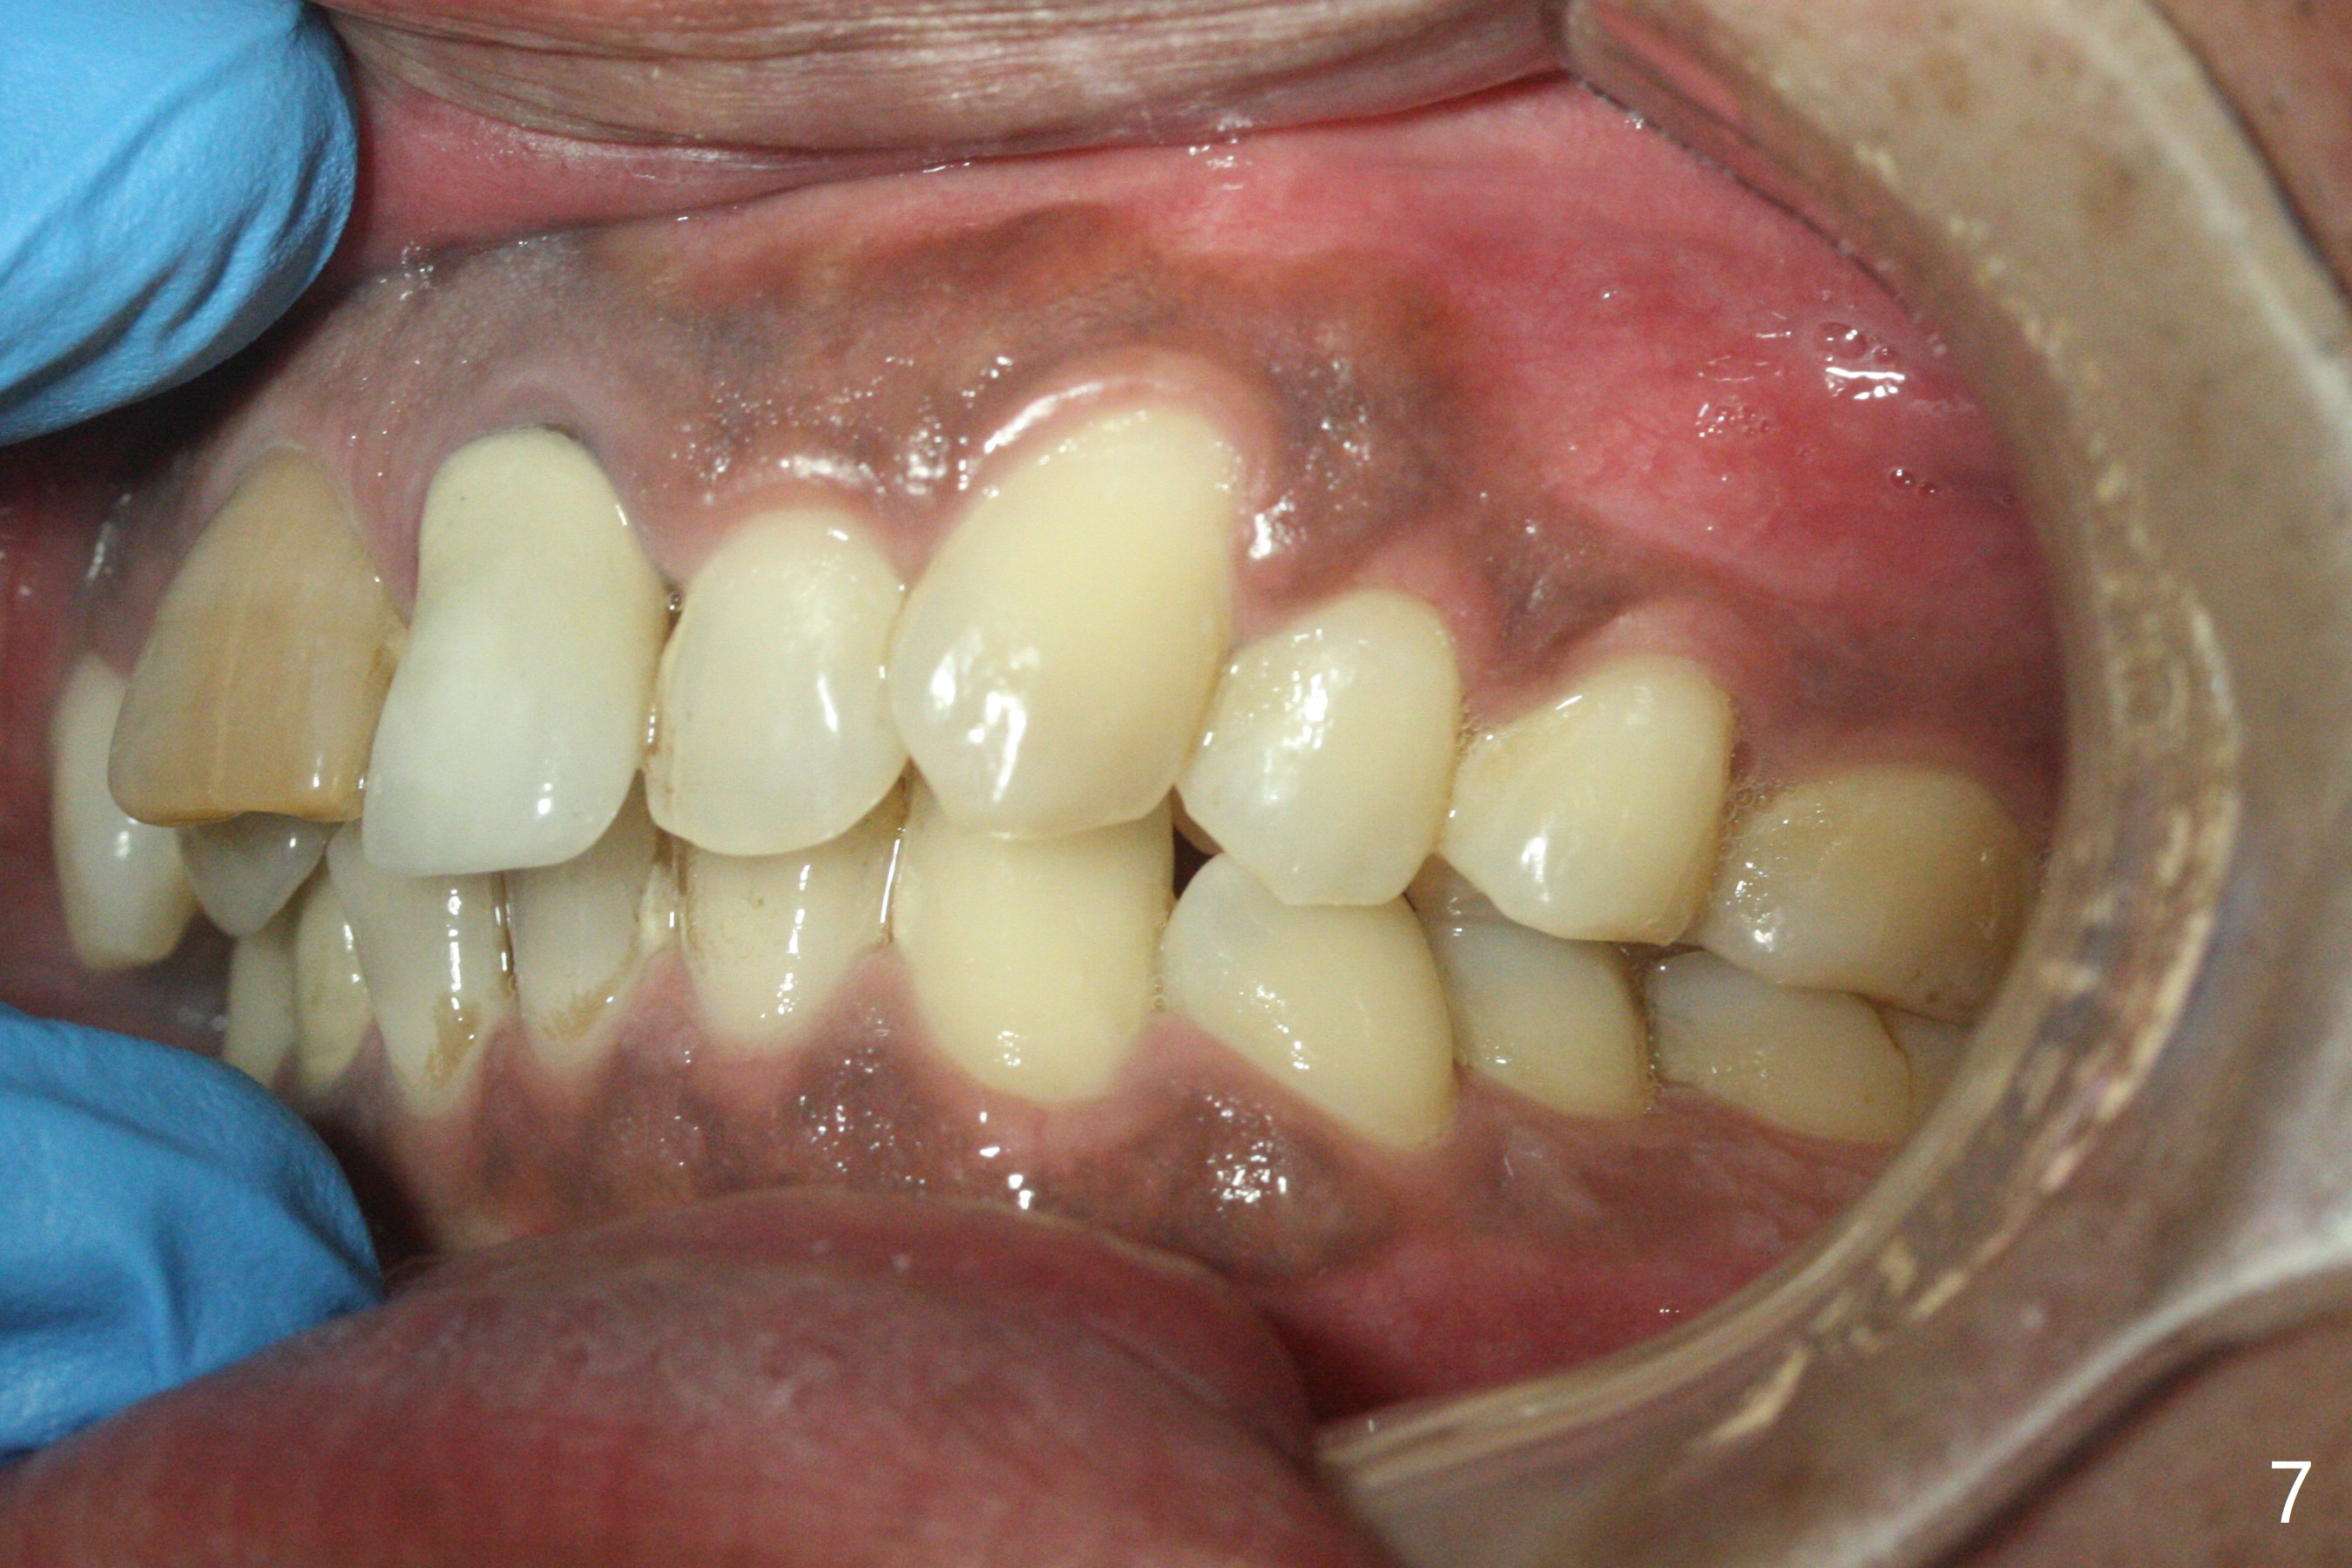

Class II半个牙。这个不用拔牙,Molar distalizaton 和expansion 就可以解决。Oral scan and submit it to Unismile. 建模后。我来帮您设计。张。两个中切牙,位置可以不用排得太完美。排到半程的位置,然后用重做的牙冠来调齐。这样,能减少一些复发的势能。Harry Hu